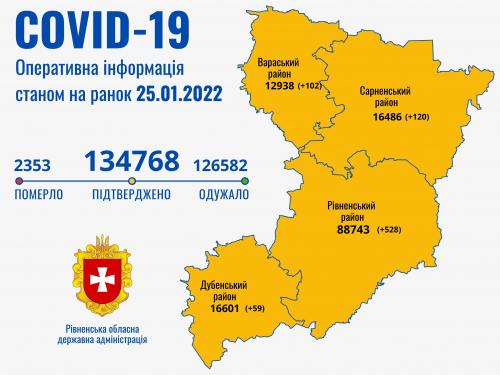

Пів тисячі - у важкому стані, 9 жителів Рівненщини померли за добу від коронавірусу